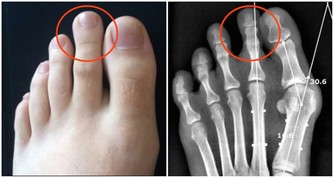

體重迅速下降且伴隨著打嗝,是腸道阻塞的標誌。如果你本來不打算減肥,體重卻在快速下降,則可能意味著你的身體沒有正確地消化你所吃的食物,醫生可能會檢查你是否患有如腸易激綜合徵、食物過敏或克羅恩病在內的疾病。另外,打嗝與體重下降同時出現,也很可能是胃癌的徵兆。